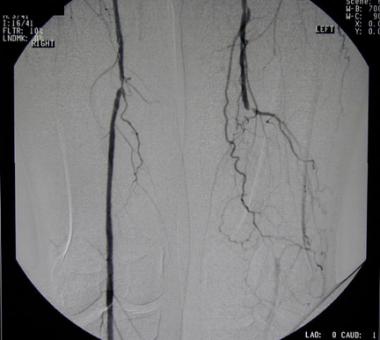

圖中可以見到逐漸阻塞的血管。

血管攝影:例如下圖為左腳PAOD的病例,可見在血管攝影下左腳血管不像右邊這麼粗,只能依靠側支循環提供下肢血流。